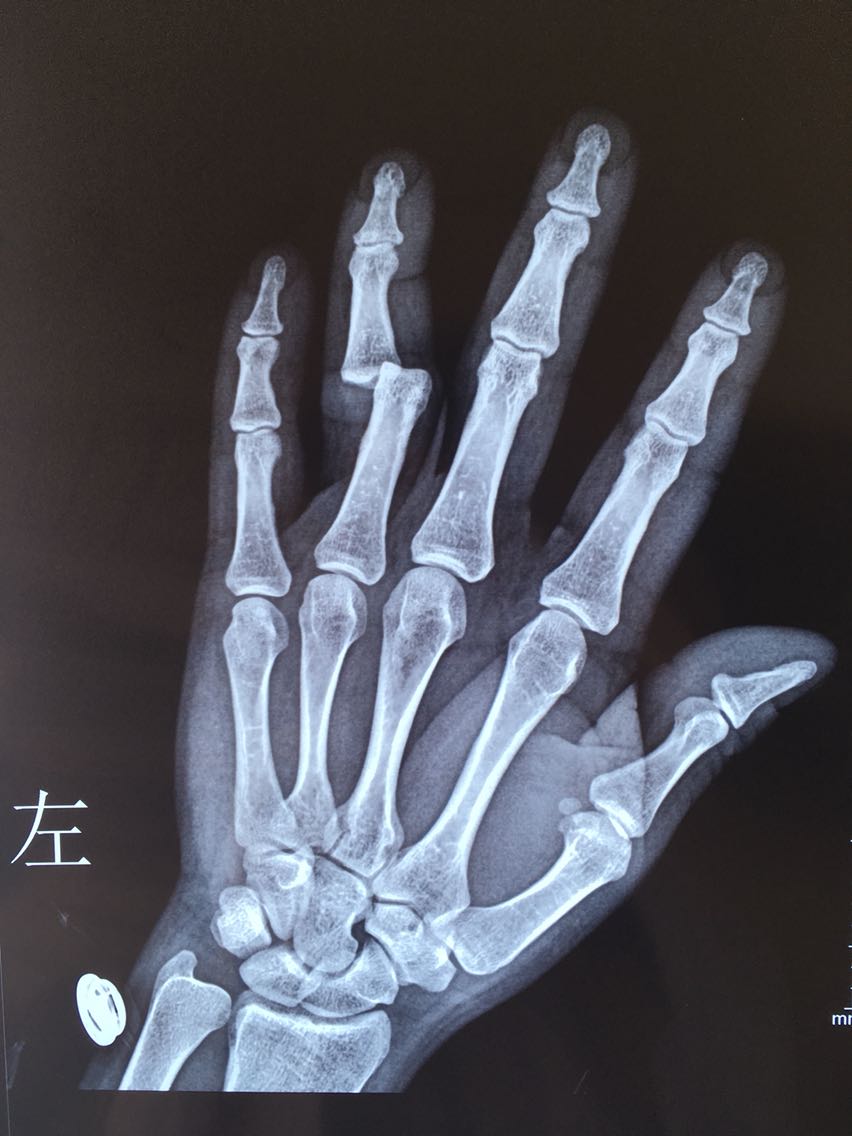

主诉:左手环指外伤后畸形伴功能障碍1小时余。 病史:患者M/30,1小时前与他人发生争执被他人扭伤左手环指,出现疼痛、畸形伴功能障碍。

查体:左手指体肿胀,近指间关节以远指体尺偏畸形,近指间关节体表触压痛阳性,近指间关节尺侧侧方应力试验阴性,桡侧侧方应力试验阳性,被动伸指成过伸样改变。

诊断:左手环指近指间关节脱位并关节囊、侧副韧带、掌板断裂 治疗:切开桡侧副韧带、关节囊缝合修复术及掌板止点金属骨锚钉重建修复术